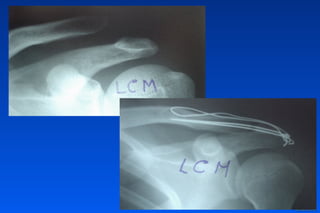

Lesión de Hill Sachs

Lesión ósea Bankart

Laxitud capsular

Signos Indirectos de Inestabilidad

Rx

Bankart

Hombro inestable

Imágen

Posición de la cabeza

humeral

Fractura de la

glenoide

Otras lesiones óseas